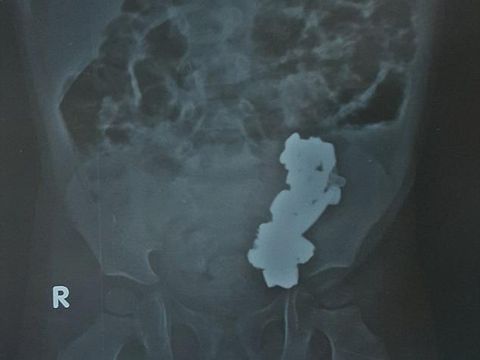

Hingg akhirnya bocah ini dibawa ke Metro Hospital, dan di sana ia menjalani pemeriksaan dengan sinar X. Dokter langsung shock begitu melihat ada setumpuk logam di dalam perut si bocah.

Tepat pada tanggal 20 November lalu, operasi pengangkatan logam digelar. Tindakan ini dipimpin oleh Dr Brahm Datt Pathak. "Total kami menemukan 29 magnet, ini sungguh tidak biasa," katanya.

Dalam operasi yang berlangsung selama tiga jam itu, Brahm juga mengeluarkan satu onderdil jam tangan dan sebuah koin.

Persoalannya, magnet-magnet ini telah menyatu dan membentuk gumpalan besar, yang kemudian memicu nyeri di dalam perut si bocah. Akibat lainnya, usus bocah asal Mathura, Uttar Pradesh ini juga mengalami kerusakan parah.

"Kalau memang logamnya kecil, tentu akan lewat begitu saja dan keluar dengan sendirinya, tapi logam-logam ini terlalu besar. Saya yakin ia sudah menahan kesakitan sejak lama," terangnya seperti dikutip dari Daily Mail, Jumat (4/12/2015).